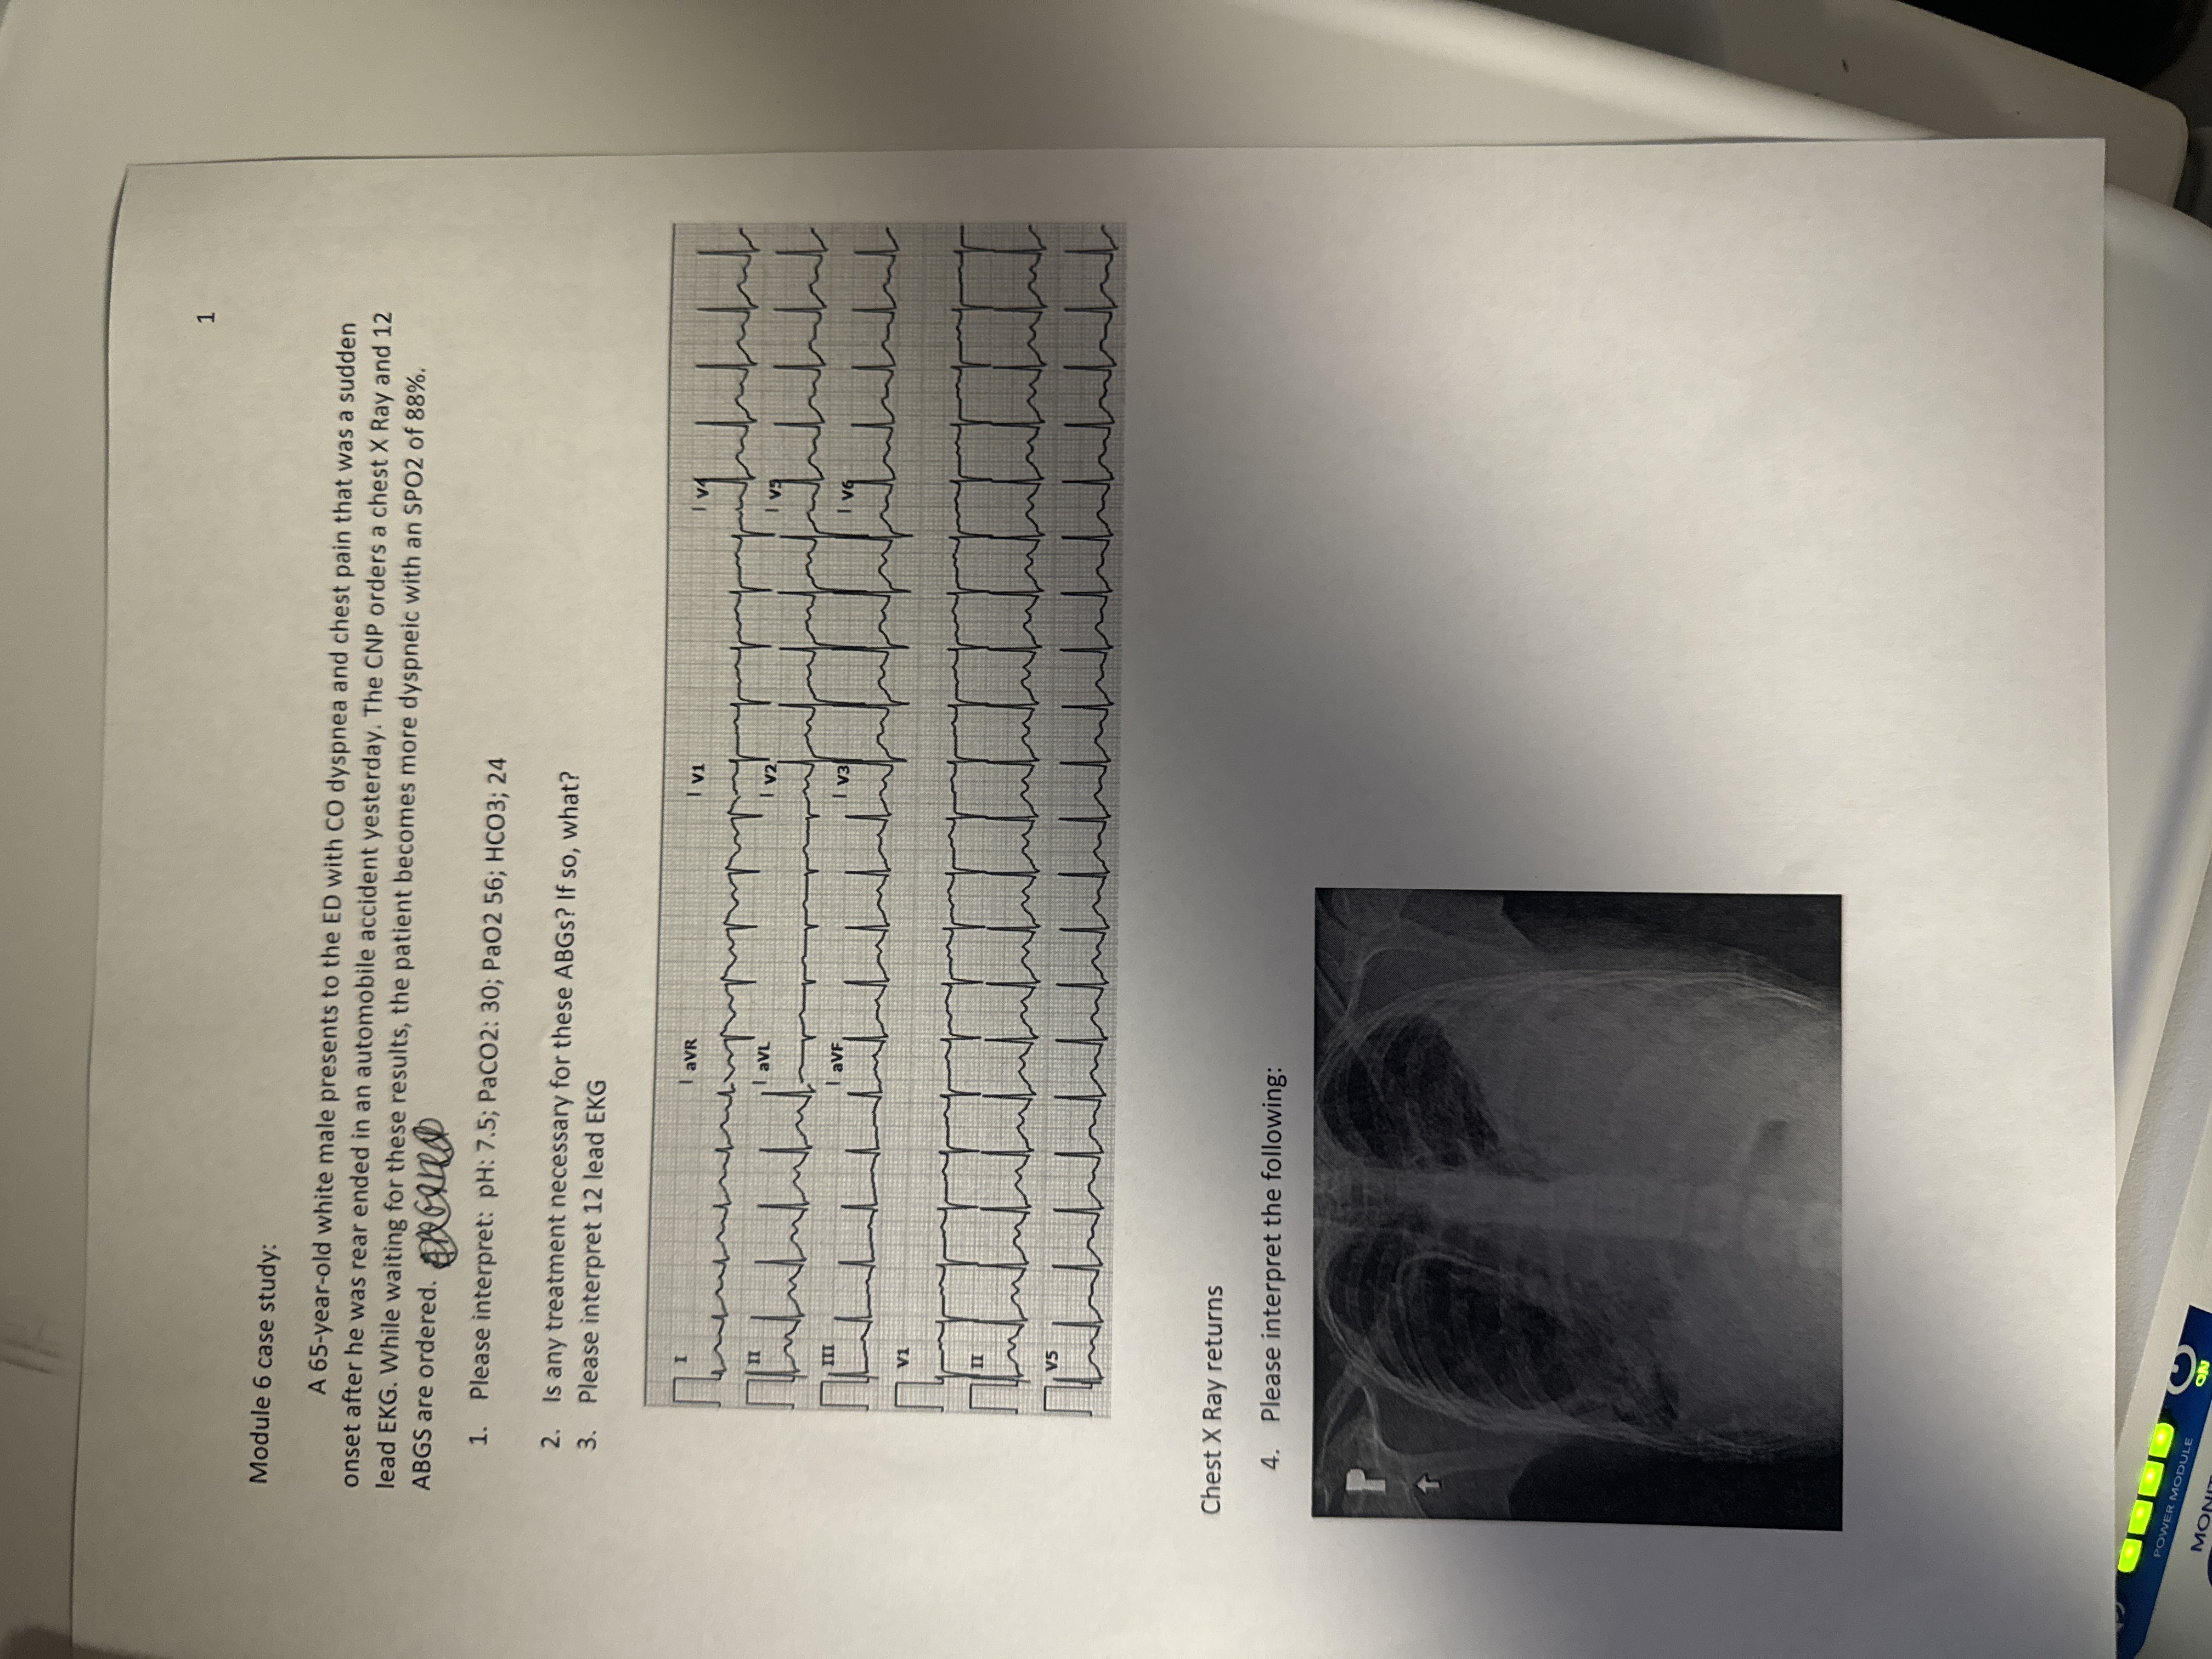

Question: Answer Module 6 case study: A 65-year-old white male presents to the ED with CO dyspnea and chest pain that was a sudden onset after